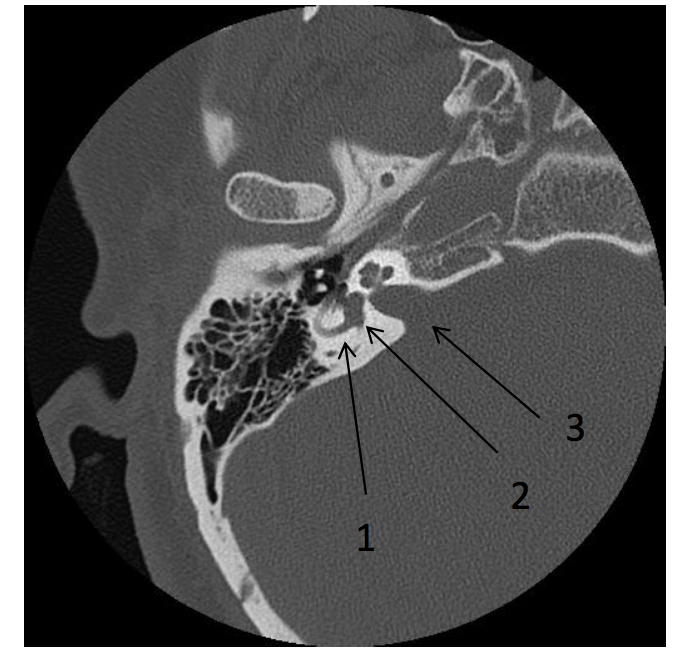

What are the labels in the image

• 1 = Lateral Semicircular Canal

What are the labeled images